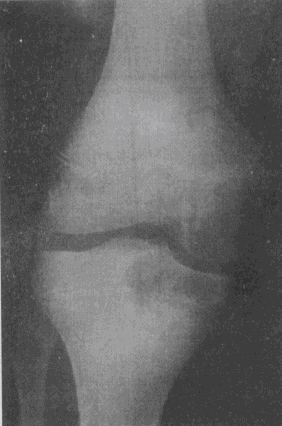

4.男,17歲。右膝關節疼痛1個月余,輕度腫脹。X線片示脛骨近端圓形骨質破壞(如圖),應考慮的診斷是

A.骨囊腫

B.骨膿腫

C.骨結核

D.骨巨細胞瘤

E.成軟骨細胞瘤

正確答案:C解題思路:骨結核大多數繼發于肺結核。結核桿菌經血行到達骨或關節,停留于血管豐富的骨松質內而發病,病理上表現為滲出、變質和增殖。